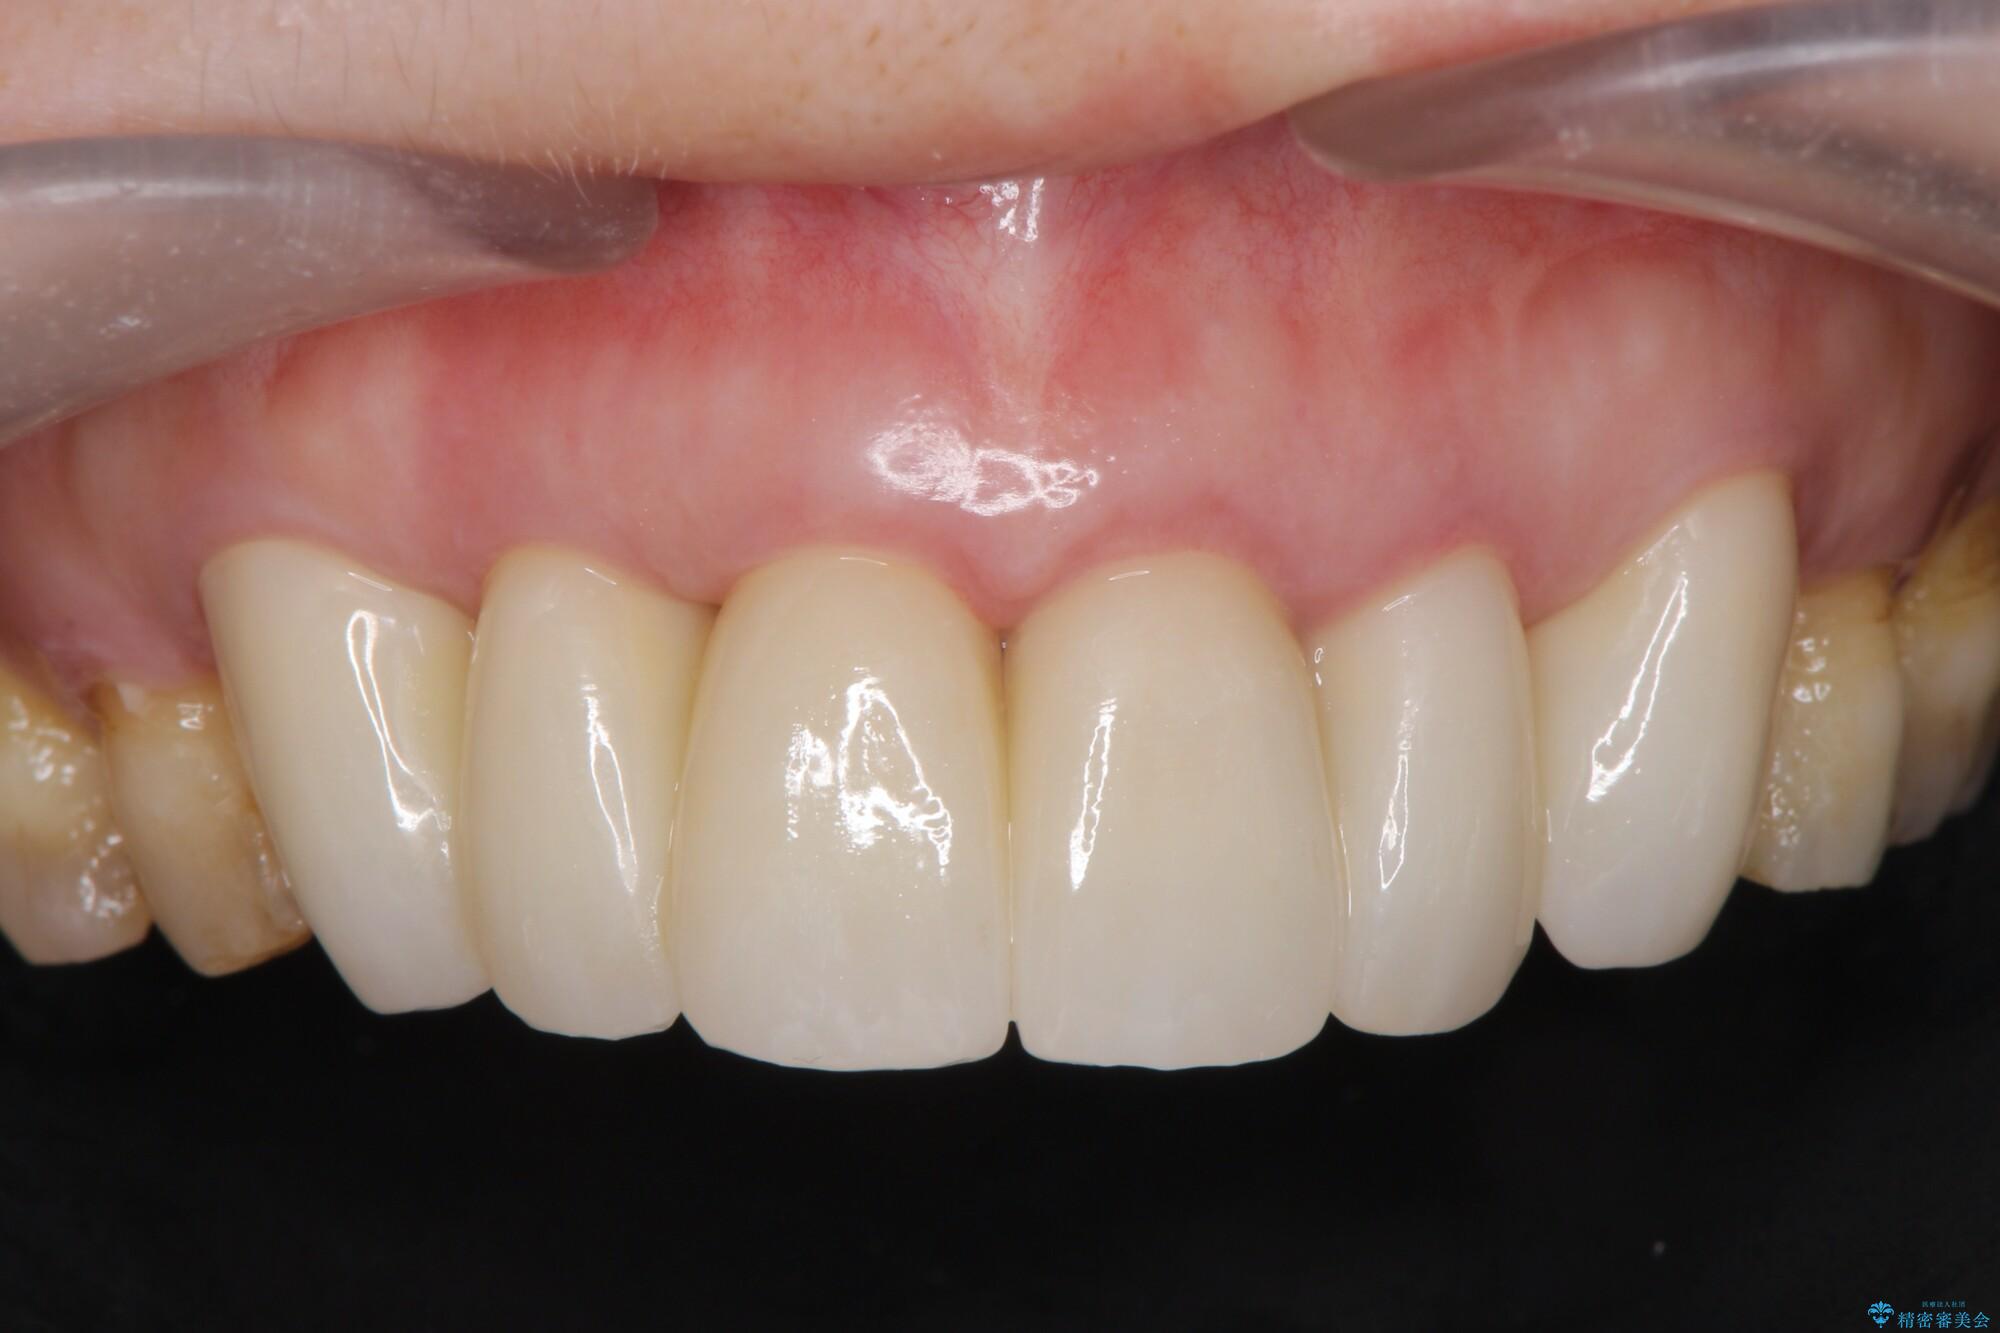

95.7万円(ジルコニアクラウン×6・仮歯×6・歯周外科)

治療後について

治療には歯肉を成熟させる期間を含めて約8ヶ月間要しましたが、出血や違和感のない歯ぐきとなり大変ご満足いただけました。